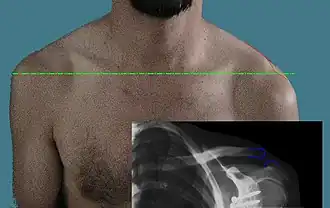

.png) | |

| An Xray showing a separated shoulder. Notice the separation between the end of the collarbone and the scapula. | |

X-ray indicates a separated shoulder when the acromioclavicular joint space is widened (it is normally 5 to 8 mm).[9]